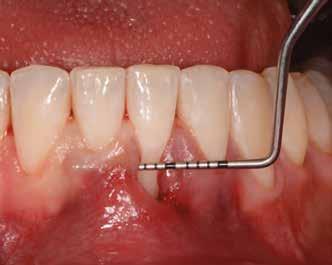

1. ábra: Műtét előtti fogászati panorámafelvétel, amelyen a hiányzó felső állcsont jobb első premolárisát és a szabad véggel rendelkező hidat láthatjuk. — 2. ábra: Az implantátum méreteinek megtervezése CBCT-vel. 3. ábra: Bukkális lágyrészdefektus. — 4. ábra: A biológiai szélesség értékelése a vertikális lágyszövetvastagság alapján. 5. ábra: Palatinális „tekercslebeny” – Palatal roll flap. — 6. ábra: Bredent medical copaSKY 4x10 implantátumbeültetés. 7. ábra: Szubkresztális implantátumbeültetés a várható biológiai szélességnek megfelelően.

(2. ábra). A lágyszövetek értékelése Seibert szerinti I. osztályú csontdefektust állapított meg (3. ábra), ezért a beavatkozáskor palatinális „tekercslebenyt” preparáltunk (palatal roll flap), és implantációt végeztünk, hogy kompenzálni tudjuk a bukkális lágyszövet-behúzódást. Megmértük a vertikális lágyszövetvastagságot, és úgy terveztük, hogy a szubkresztális implantátum beültetése összhangban legyen a biológiai szélesség kialakulásával a transzgingivális gyógyulási periódus alatt (4. ábra)